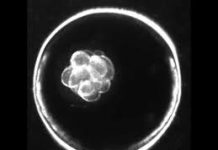

The Bioethicist and the Embryo

(This is one instalment of a four-part series on the human embryo by Dr. Eshan Dias. We are posting the third part of the...